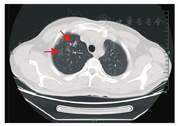

病例1,男,34岁,浙江仙居人,因"发热、腹痛40 d,咳嗽、咳痰1个月"于2019年7月17日收治浙江大学医学院附属第一医院感染科。患者40 d前出现发热,高达39℃,伴腹痛及腹泻,为黄色稀便。至当地医院就诊,诊断为急性胃肠炎,予以静脉输液治疗,体温恢复正常,但仍有腹痛、胀痛,程度较前减轻,未再腹泻。2周前出现咳嗽、咳痰,咳嗽剧烈时伴气促,并伴发热38℃,体温可自行降至正常。再次至当地医院就诊考虑"肺部感染",予以补液及激素治疗,效果不佳。遂至我院门诊以"发热待查"收入。体格检查:体温37.2℃,脉搏101次/min,呼吸19次/min,血压127/92 mmHg(1 mmHg=0.133 kPa)。神志清,精神可,皮肤黏膜及巩膜无黄染,无皮疹,双下肺呼吸音低,未闻及啰音,心律齐,无杂音。腹软,无压痛及反跳痛。双下肢无水肿,病理征未引出。入院诊断:肺部感染。入院后查血常规:白细胞计数22.6×109/L,嗜酸性粒细胞占比0.687,嗜酸性粒细胞15.51×109/L。红细胞沉降率(ESR)63 mm/1 h,C-反应蛋白(CRP)24.1 mg/L。粪便常规正常。头颅CT未见明显异常,腹部CT示腹膜弥漫性增厚,盆腔少许积液、脾大。肺部CT示两侧胸腔积液伴两肺下叶萎陷,显示感染(图1)。追问病史发现48 d前曾生食野生螃蟹史,查血寄生虫抗体示并殖吸虫抗体阳性。诊断:并殖吸虫病(腹型+肺型)。予吡喹酮片25 mg/kg,2次/d,口服3 d,腹痛消失,咳嗽咳痰缓解后出院。出院后2周当地医院复查患者无不适,血常规:白细胞计数14.9×109/L,嗜酸性粒细胞占比0.468,嗜酸性粒细胞6.98×109/L,血红蛋白144 g/L,血小板计数332×109/L。肺部CT示两肺感染性病变较前明显吸收。

注:右上肺可见斑片状高密度影,边缘不清,内密度不均匀(箭头示)